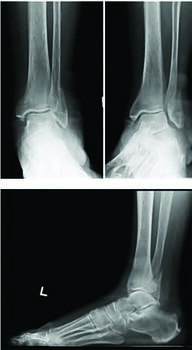

Taking it a step further in identifying biomechanical failures with fixation and possibly early weight-bearing, Tan and colleagues similarly performed a cadaveric study to evaluate the biomechanics of early weight-bearing after surgical fixation of unstable ankle fractures. Secondarily, these authors wanted to evaluate the amount of displacement with early loading and correlate displacement with bone mineral density.11 Researchers divided 24 fresh frozen cadavers into three groups: Group 1, bimalleolar ankle fractures (n=6); Group 2, trimalleolar ankle fractures without posterior malleolar fixation (n=9); and Group 3, trimalleolar ankle fractures with fixated posterior malleolar fractures. Fracture fixation was with a 3.5mm interfragmentary screw and a neutralization locking compression fibular plate with three, proximal 3.5mm non-locking screws and four, distal 2.7mm locking screws. Posterior malleolar fracture fixation was with one, 4.0 mm partially-threaded cannulated screw. Medially malleolar fracture fixation was with with two, 4.0 mm partially-threaded cannulated screws. Specimen exposure to axial compression loading simulated the load of adult weight-bearing. With each simulated ankle fracture group (bimalleolar, trimalleolar with and without posterior malleolar fixation), there was no significant fracture displacement and no displacement or failure of hardware failure.11 In terms of secondary outcomes, there was no correlation between fracture displacement and bone mineral density. Overall, the authors supported early weight-bearing protocols after fixation of unstable ankle fractures.11

The traditional postoperative course following ankle fracture ORIF is non-weight-bearing cast immobilization. This is generally due to a fear of construct failure prior to osseous healing.11 However, early weight-bearing might expedite an earlier return to work, subsequently minimizing the economic impact of fractures and lessening altered gait mechanics.11

There is a substantial amount of literature that supports early weight-bearing after ankle fracture ORIF. An important article by Ahl and colleagues utilized a prospective, randomized controlled trial to compare patients undergoing isolated fibular ankle ORIF with pins, cerclage wires, and staples.12 The control group remained non-weight-bearing in a below-knee cast until postoperative week four, and the experimental group began weight-bearing on postop day one in a below-knee cast. The authors concluded that there was no significant difference in loss of reduction based on radiographic findings at 12 and 24 weeks, and no difference in swelling and range of motion (ROM) among both groups with minimal fixation constructs such as cerclage wire and staples.12 Similarly, a year later, Ahl and colleagues evaluated and compared patients with bimalleolar and trimalleolar ankle fracture ORIF with immediate weight-bearing on postoperative day one in a below-knee cast versus non-weight-bearing for four weeks.13 Again, the authors found no difference in loss of reduction between the two groups and no difference concerning swelling or range of motion with similar constructs of cerclage wire, pins, or staples.13 On a larger scale, a Cochrane meta-analysis of three studies compared early and late weight-bearing after ankle fracture fixation.14,15 Among these studies, there was no significant difference in functional scores, range of motion, or radiographic outcomes after weight-bearing.14-16